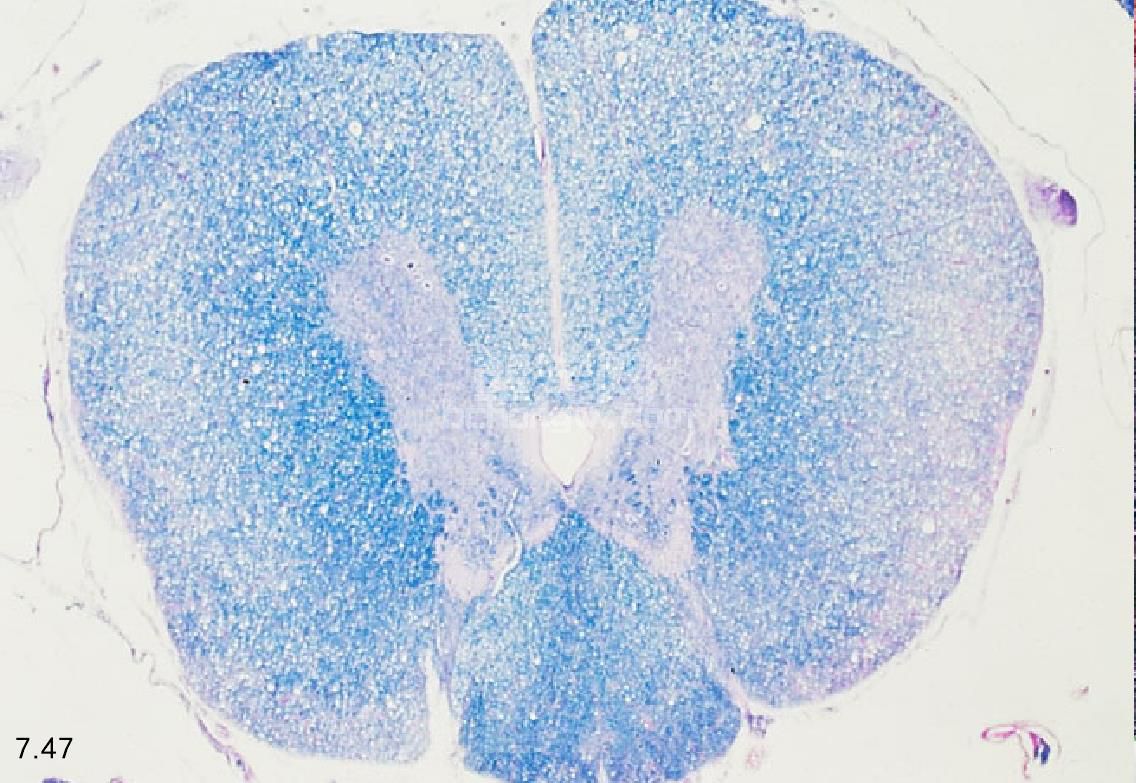

临床症状 临床症状的出现不易察觉,为缓慢的进行性疾病。起初的症状包括后肢共济失调和带有意识性固 有感觉丧失的轻瘫(图7.47和图7.48)。痛觉、前肢功能和反射正常,且少见大小便失禁。可出现后肢脊髓反射 过度,但若神经根受累也可能无反射。

图7.47和图7.48 患退行性脊髓病德国牧羊犬的胸段脊髓横断(x50)。图7.48为脊柱的特征性病变。